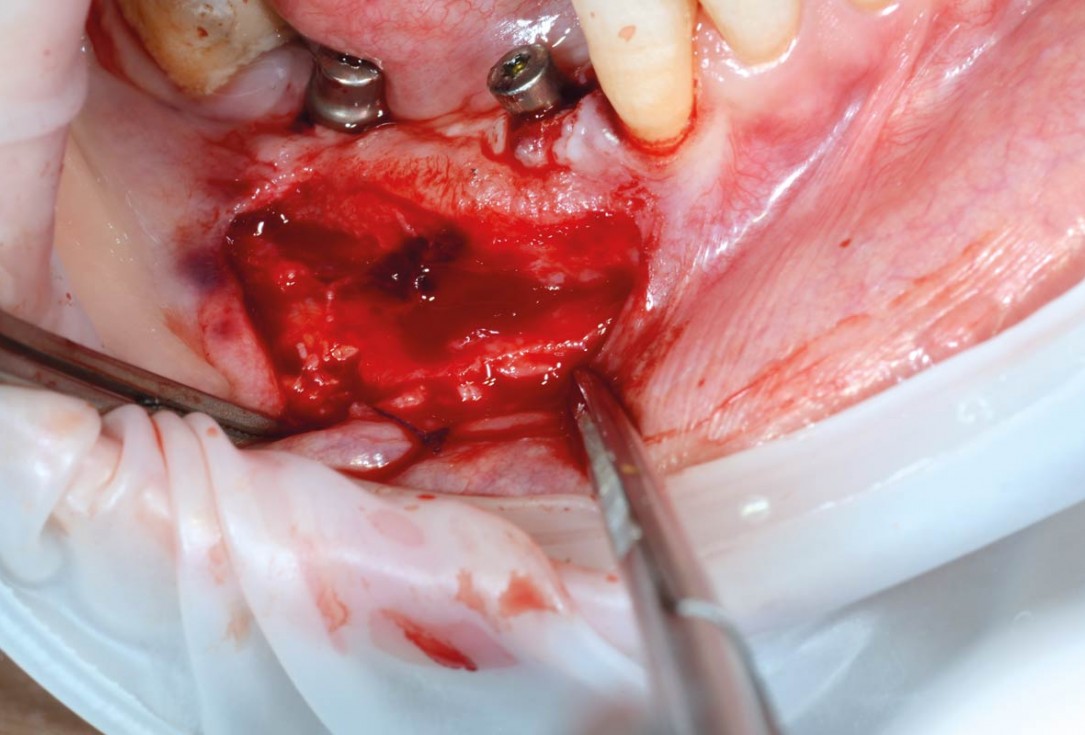

03/29 - Preparation of a full-thickness flapVertical bone augmentation and broadening of attached gingiva using cerabone®, permamem® and mucoderm® - Dr. R. Naimoli

04/29 - Clinical view after exposure of the defect, to promote healing the local bone was perforatedVertical bone augmentation and broadening of attached gingiva using cerabone®, permamem® and mucoderm® - Dr. R. Naimoli